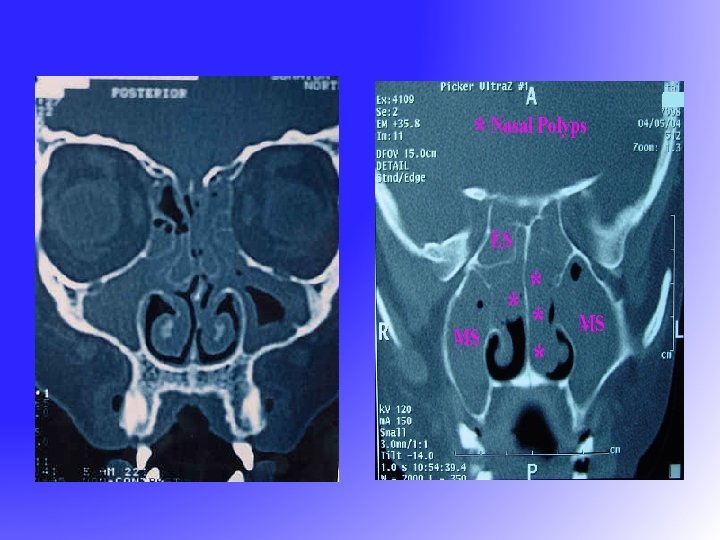

FESS • Functional Endoscopic Sinus Surgery – resume the normal function of sinus • drainage • ventilation • Messerklinger 1960 s – sinus mucus drain in a genetically determined path to the natural ostium

FESS • Functional Endoscopic Sinus Surgery – resume the normal function of sinus • drainage • ventilation • Messerklinger 1960 s – sinus mucus drain in a genetically determined path to the natural ostium